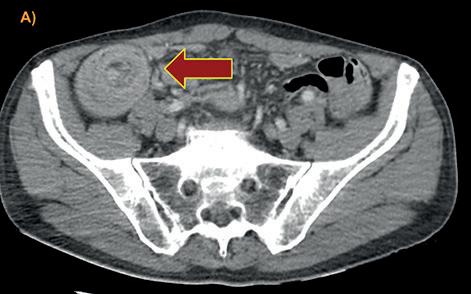

FIGURA 1: TOMOGRAFÍA DE ABDOMEN Y PELVIS CON CONTRASTE EV: En topografía pancreático-duodenal se observa una voluminosa tumoración de contornos lobulados con ligera heterogeneidad central, de 7,3 cm. podría corresponder a gran conglomerado adenopático. En el retroperitoneo y en el mesenterio, se observan múltiples ganglios con leve a moderado aumento de tamaño. En el hemiabdomen derecho se observa una tumoración voluminosa, asociada a una invaginación en topografía cecoascendente.

A)-B)Signo de donut o escarapela.C). Signo de la salchicha o psudoriñon. A); B) Signo de donut o escarapela. C). Signo de la salchicha o psudoriñon. D) Corte coronal. Servicio de Tomografía, Departamento de Imágenes, Hospital de Clínicas “Jose de San Martin” [Av. Córdoba 2351, CABA].